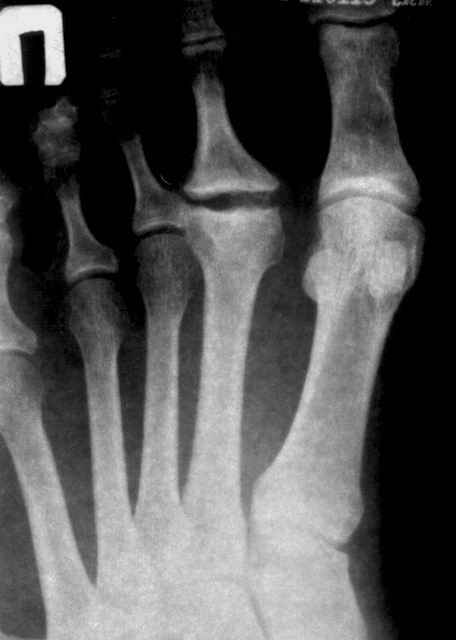

У меня была похожая пациентка - тоже с вальгусной деформацией, неуточненная травма 3 года назад. Обратилась по поводу болей в области головки 2 плюсневой кости, в течение 2-х месяцев. При осмотре - небольшая припухлость, движения в суставе в полном объеме, даже некоторая "разболтанность" отмечается. Боли усиливались в основном при ходьбе на каблуке, когда увеличивалась нагрузка на головку плюсневой кости. У неё были более выраженные изменения на Rg-грамме (во вложении), а здесь - только если в прямой проекции (справа) можно заподозрить некоторую уплощенность головки...

Уважаемые коллеги, асептический некроз головки 2 плюсневой кости - болезнь Фрайберга. По сути, чтобы избавиться от болей в данном суставе, хватает резекции головки. Консервативно - дипроспан. Хотя принимая во внимание вальгусную деформацию 1 пальца и молоткообразную деформацию 2 пальца, предпочтительно все же предложить пациенту реконструкцию переднего отдела стопы. Судя по снимку, латеральная сесамовидная кость полностью вывихнута в 1 межпальцевый промежуток - следовательно, нужна остеотомия 1 плюсневой кости. Шеврон или скарф. 2 палец - резекция головки 2 плюсневой кости + Гоман.

если бы речь шла о чистой остеохондропатии, то мне мысли Юлии Олеговны казались бы ближе всех к истине, но давайте обратим внимание на боковую проекцию: кто-нибудь видит какие-либо изменения, кроме углового смещения головки в подошвенную сторону?

Мне картина видится такой: жил себе пациент с молоткообразным ІІ пальцем, что характерно при такой вариации в длине I и II плюсневых костей, это и вызывало боли в ступне. Месяц назад "придавил" II пфс радиатором, получил перелом головки ІІ пястной кости с подошвенно-угловым смещением (приложение силы основной фаланги ІІ пальца), сейчас перелом почти сросся (линия перелома еще слегка прослеживается).